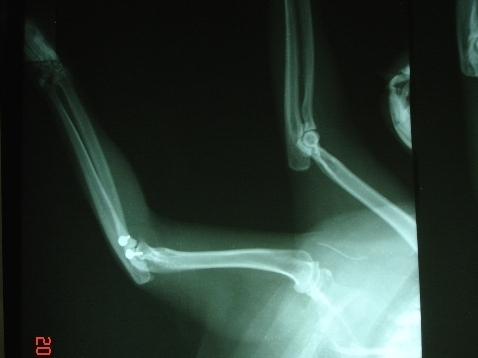

- 編號: 608

主題: 三花妹妹左手骨折脫臼 申請者姓名: 張嘉盈 花色: 申請日期: 2012-07-16 16:40:23 申請者部落格: 申請者臉書網址: https://www.facebook.com/media/set/?set=a.467340686611939.111247.100000080346180&type=3#!/photo.php?fbid=467341476611860&set=a.467340686611939.111247.100000080346180&type=3&theater 所在縣市/合作醫院: 新北市/五信動物醫院 治療費用: 35000元 需求人數: 38人 已結案 (2013-06-27 13:21:47) 報名人員: kelly(已付款)、Nico Liu(已付款)、won889(已付款)、高永顗(已付款)、valen、sandy_huanglichuan(已付款)、Clare Chen(已付款)、mimicat(已付款)、桑華、smountains(已付款)、Bei Bei Wang(已付款)、多蕊咪(已付款)、Irena(已付款)、rober(已付款)、maggie(已付款)、Diamond(已付款)、許盈仙(已付款)、Freya(已付款)、UNA、hide(已付款)、lucy(已付款)、許惠雯(已付款)、蠢蚱蜢(已付款)、Marquise Li(已付款)、玻利絲(已付款)、Pierce(已付款)、purism(已付款)、smilecat(已付款)、Juno388(已付款)、Veara Lin(已付款)、Slowsnow Hsu(已付款)、Kero Yen(已付款)、cenry(已付款)、OLivia Lee(已付款)、Juli Cheng(已付款)、amelie(已付款)、Ethan Chang(已付款)、anihhn(已付款)、董成瑜(已付款)、Albert、Giselle Hsieh、小舟、小舟、Emily Chou x2(已付款)、 候補人員: 動物病情說明: 三花乖乖是愛媽在餵養的浪貓,某天發現他的左腳畸形,本來醫師預以石膏固定,麻醉後推不回去,原來是罕見的連韌帶也斷裂,基於韌帶斷裂需要的手術耗材特殊,五信醫師特別向台大調耗材,約等1星期,期間邦乖乖坐止痛楚哩,6月初已植入鋼板固定,至今已換過3次固定版,目前恢復良好,約休養3個月就可痊癒,五信醫師特別給予浪貓醫療折扣優惠,目前仍在住院送養中,術前一星期(等待耗材的時間)及手術1個月之後的住院費用由救援志工自行吸收,懇請大家一同幫忙,也歡迎大家前往探視認養。